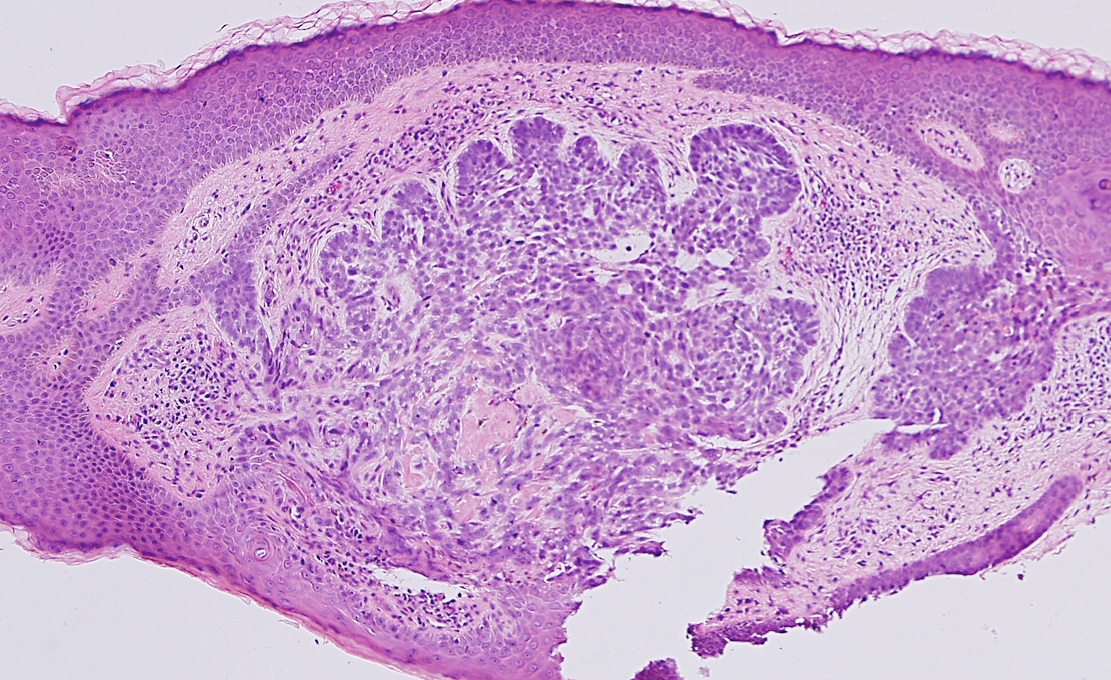

VA115: Right Cheek, Basal Cell Carcinoma, Nodular

- * indicates area of liquifactive necrosis/cyst with remnant necrotic cell debris